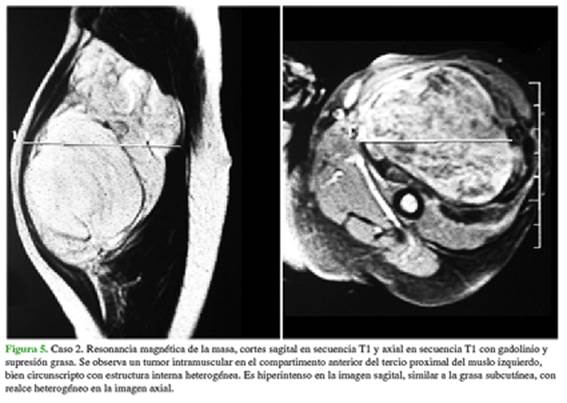

Los estudios ecográficos suelen ser la primera línea de investigación por su disponibilidad y porque no requieren sedación ni anestesia:13,14 en 16 de nuestros pacientes fue el primer estudio. En contrapartida, la RM distingue fácilmente los componentes adiposos del lipoblastoma, así como los componentes quísticos y la vascularidad, aproximando mucho el diagnóstico;14 en esta serie, también 16 pacientes fueron estudiados con RM (Figura 5).